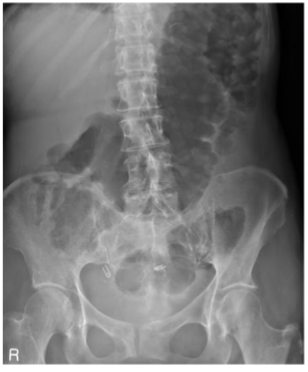

What is this and what type of scan

small bowel obstruction/ileus, abx